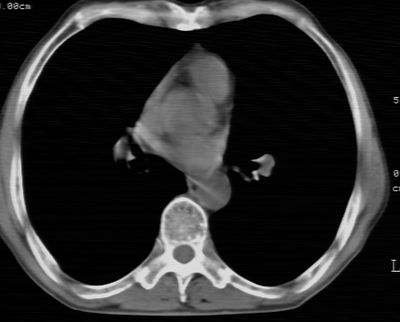

标题: CT24783:m71,既往肺心病史3年,现咳嗽,憋喘。 [打印本页]

标题: CT24783:m71,既往肺心病史3年,现咳嗽,憋喘。

1、左肺上叶spn,毛刺+分叶+血管集束征,考虑周围型肺癌可能性大

2、全小叶性肺气肿。

1)左肺上叶周围型肺癌可能。2)两肺全小叶型肺气肿。